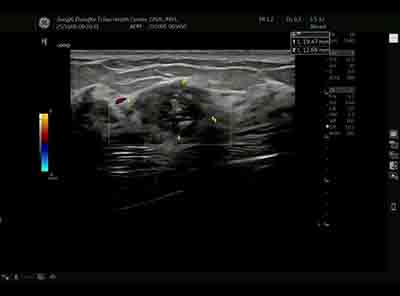

血流模式的精細評估 乳腺良惡性腫瘤的血流特征存在顯著差異。E11采用的超微細血流成像技術具有突破性意義:

準確區分腫瘤邊緣與內部血流分布 惡性腫塊通常表現為血流豐富、走行紊亂、動靜脈瘺形成,而良性病變血流相對稀疏、走行規則。這種差異為鑒別診斷提供了重要參考。